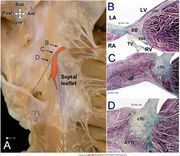

| 10:46, 18 May 2012 | Figure 4.jpg (file) |  |

566 KB | 1 | |